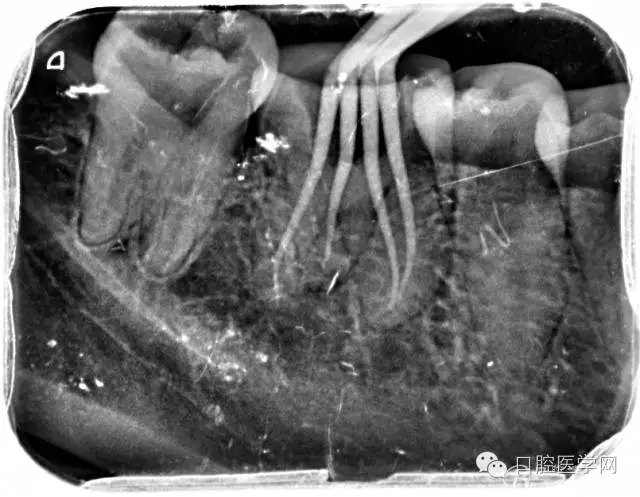

根管的解剖界限是从髓室根管入口到根尖部牙本质- 牙骨质交界处(生理性根尖孔) 。理想的根管充填应该是对生理性根尖孔冠方以上进行严密的三维封闭。临床上根据X线牙片判断根管充填的质量。牙片上充填材料与根管壁紧密接触一般被认为充填严密。关于充填止点,由于牙本质- 牙骨质界离根尖孔外表面平均距离为0. 5~0. 7 mm,同时相当多的根尖开口并不位于X线片的根尖处。因此临床上认为材料充填至距X线片牙根最尖端0. 5~1 mm (也有认为0. 5~2mm)为适填。

5、根管充填的技术方法

为达到更为理想的根充效果,研究人员和牙髓病医生一直在探索根管充填技术,并且发展出多种可供选择的方法。Ingle]将其归纳为3 类: ①“牙胶尖+封闭剂”式; ②“根尖1 /3充填”式; ③“注射或螺旋充填”式。目前临床广泛采用的主要是“牙胶尖+封闭剂”方式。按照充填压力的方向(侧向或垂直)不同和牙胶温度(冷或热)不同,根管充填有2 种基本技术:冷牙胶侧方加压充填和热牙胶垂直加压充填。现有的各种充填方法均是这2 种基本方法基础上的发展或改良。医生可根据方法的优缺点以及个人习惯选择使用。